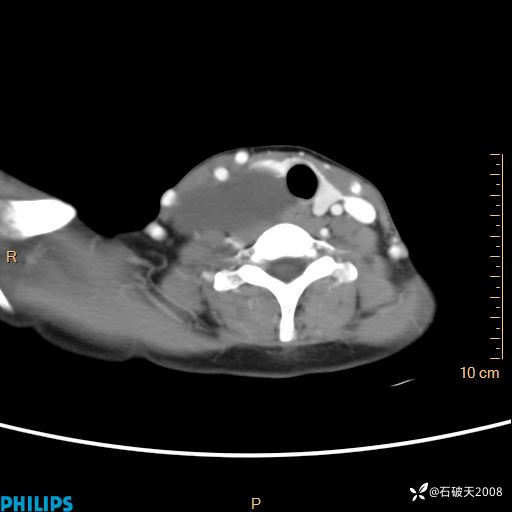

影像诊断要密切结合临床,真的很有必要(病理已公布)

女 21岁 主 诉:发现右侧颈部肿物18年余。

现病史:18年余前患者无明显诱因发现颈部偏右侧有一肿物,具体大小不明确,咳嗽、憋气时肿物增大,局部无疼痛,无吞咽不适,无胸闷及呼吸困难,至当地医院检查考虑良性病变(具体不详)并未做特殊处理,现患者自觉肿物随年龄增长而进一步变大,今日至我院行颈部CT平扫+增强提示:1.右侧颈根部、锁骨上窝及纵隔内异常密度影,考虑良性病变,淋巴管瘤?囊肿?请结合临床。2.双侧颈部小淋巴结。建议结合临床及其他相关检查。现为行进一步治疗,门诊以“颈部局部肿物”为诊断收住我科,发病来患者神志清,精神可,饮食睡眠可,大小便正常,体重无下降。

静脉期